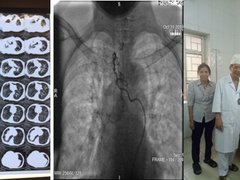

Những nỗ lực giành giật mạng sống từ tay tử thần

Không ít những ca cấp cứu hy hữu trong năm 2019 đã được đội ngũ y bác sĩ thực hiện. Sự sống và cái chết nhiều lúc chỉ là những lằn ranh mỏng manh.

13/11/2019 16:17:27